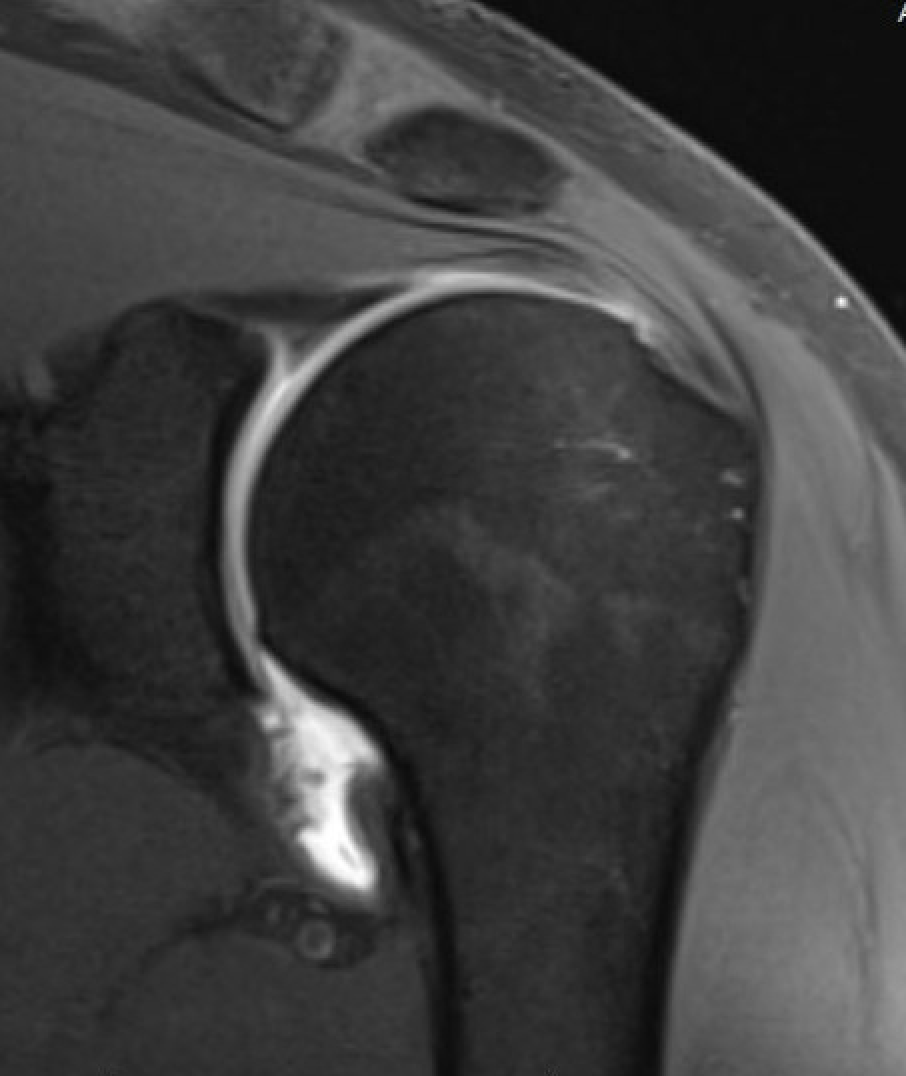

MRI

| Normal | HAGL / J Sign |

U shaped appearance Normal IGHL insertion on the humeral neck |

J shaped Avulsion of the IGHL |